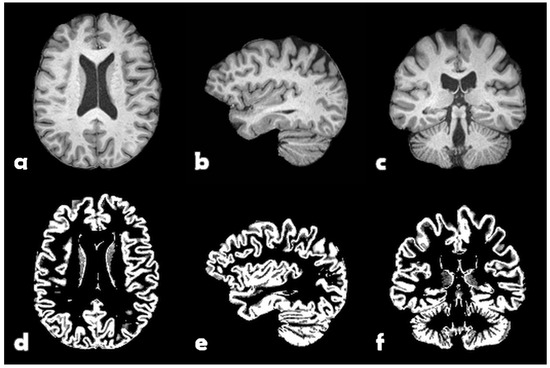

The subjects were divided 70%/15%/15% for training, validation, and testing, respectively. The combined set of training and validation was partitioned in 3 different ways with mutually disjoint validation sets for cross-validation purposes. FSL FAST [33] was used for each skullstripped volume to obtain maps of grey matter. See Figure 2 for one example subject. These grey matter volumes were zero-padded, symmetrically, to match the largest grid size, resulting in volumes of 256 × 256 × 208 voxels with a size of 1 × 1 × 1 mm 3 .

Figure 2. One example subject from U.K. Biobank. Top: Preprocessed T1-weighted volume: (a) transversal slice, (b) sagittal slice, and (c) coronal slice. Bottom: Grey matter probability map: (d) transversal slice, (e) sagittal slice, and (f) coronal slice.